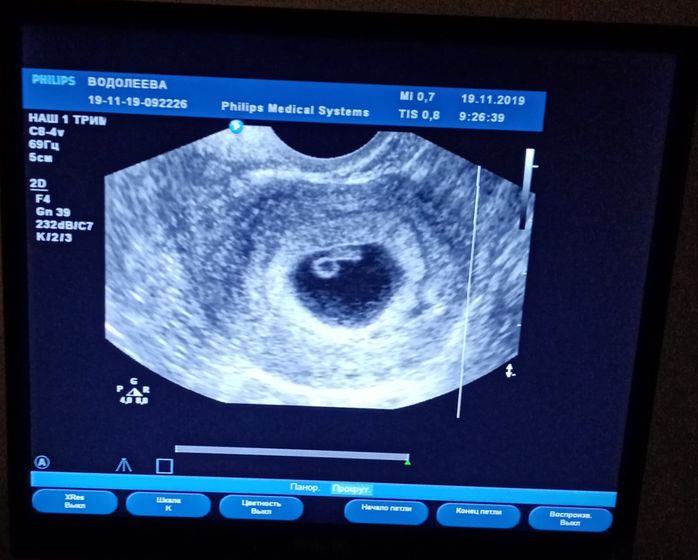

Сегодня была на повторном узи. Девочки, я плакала, когда увидела уже подросшего малыша-5,8мм и впервые услышала наше сердечко-117уд/мин! 6недель 3 дня✌️ждем с нетерпением нашу кроху???